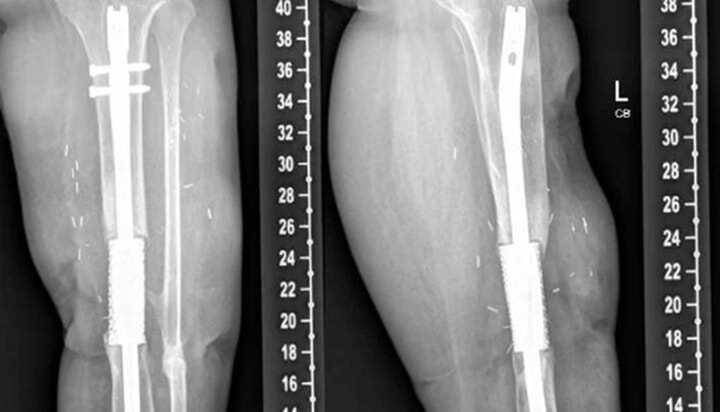

近日,魔猴網(wǎng)了解到,最近在《Cureus》雜志上發(fā)表了一份題為“Treatment of an Infected Tibial Shaft Non-Union Using a Novel3D-Printed Titanium Mesh Cage: A Case Report”的病例報(bào)告,這項(xiàng)報(bào)告介紹了一件使用新型 3D 打印鈦網(wǎng)籠植入物成功治療受感染的脛骨不愈合(non-union)疾病的醫(yī)療案例。